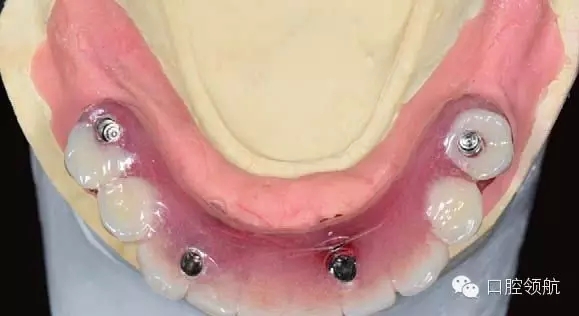

手術(shù)當天取模,當天灌注石膏模型,上牙合架,開始準備制作螺絲固定的過渡義齒(圖6-11,圖6-12)。

5.webp.jpg

圖6-11 安放閉口轉(zhuǎn)移桿后的牙合面照

6.webp.jpg

圖6-12 下頜All-on-4取模后照片

圖6-11可見前牙區(qū)轉(zhuǎn)移桿與后部轉(zhuǎn)移桿之間有十幾度的角度偏差,前牙區(qū)沒有使用角度復合基臺來調(diào)整角度。雖然可以使用17°的角度復合基臺調(diào)整螺絲開孔角度,使前部及后部的就位道更接近平行,但是因為這樣就加大了前牙區(qū)的義齒厚度,容易造成舌體的不適,因此下前牙區(qū)在使用角度復合基臺調(diào)整過于唇傾的種植體方向時,需要慎重并事先與患者溝通。